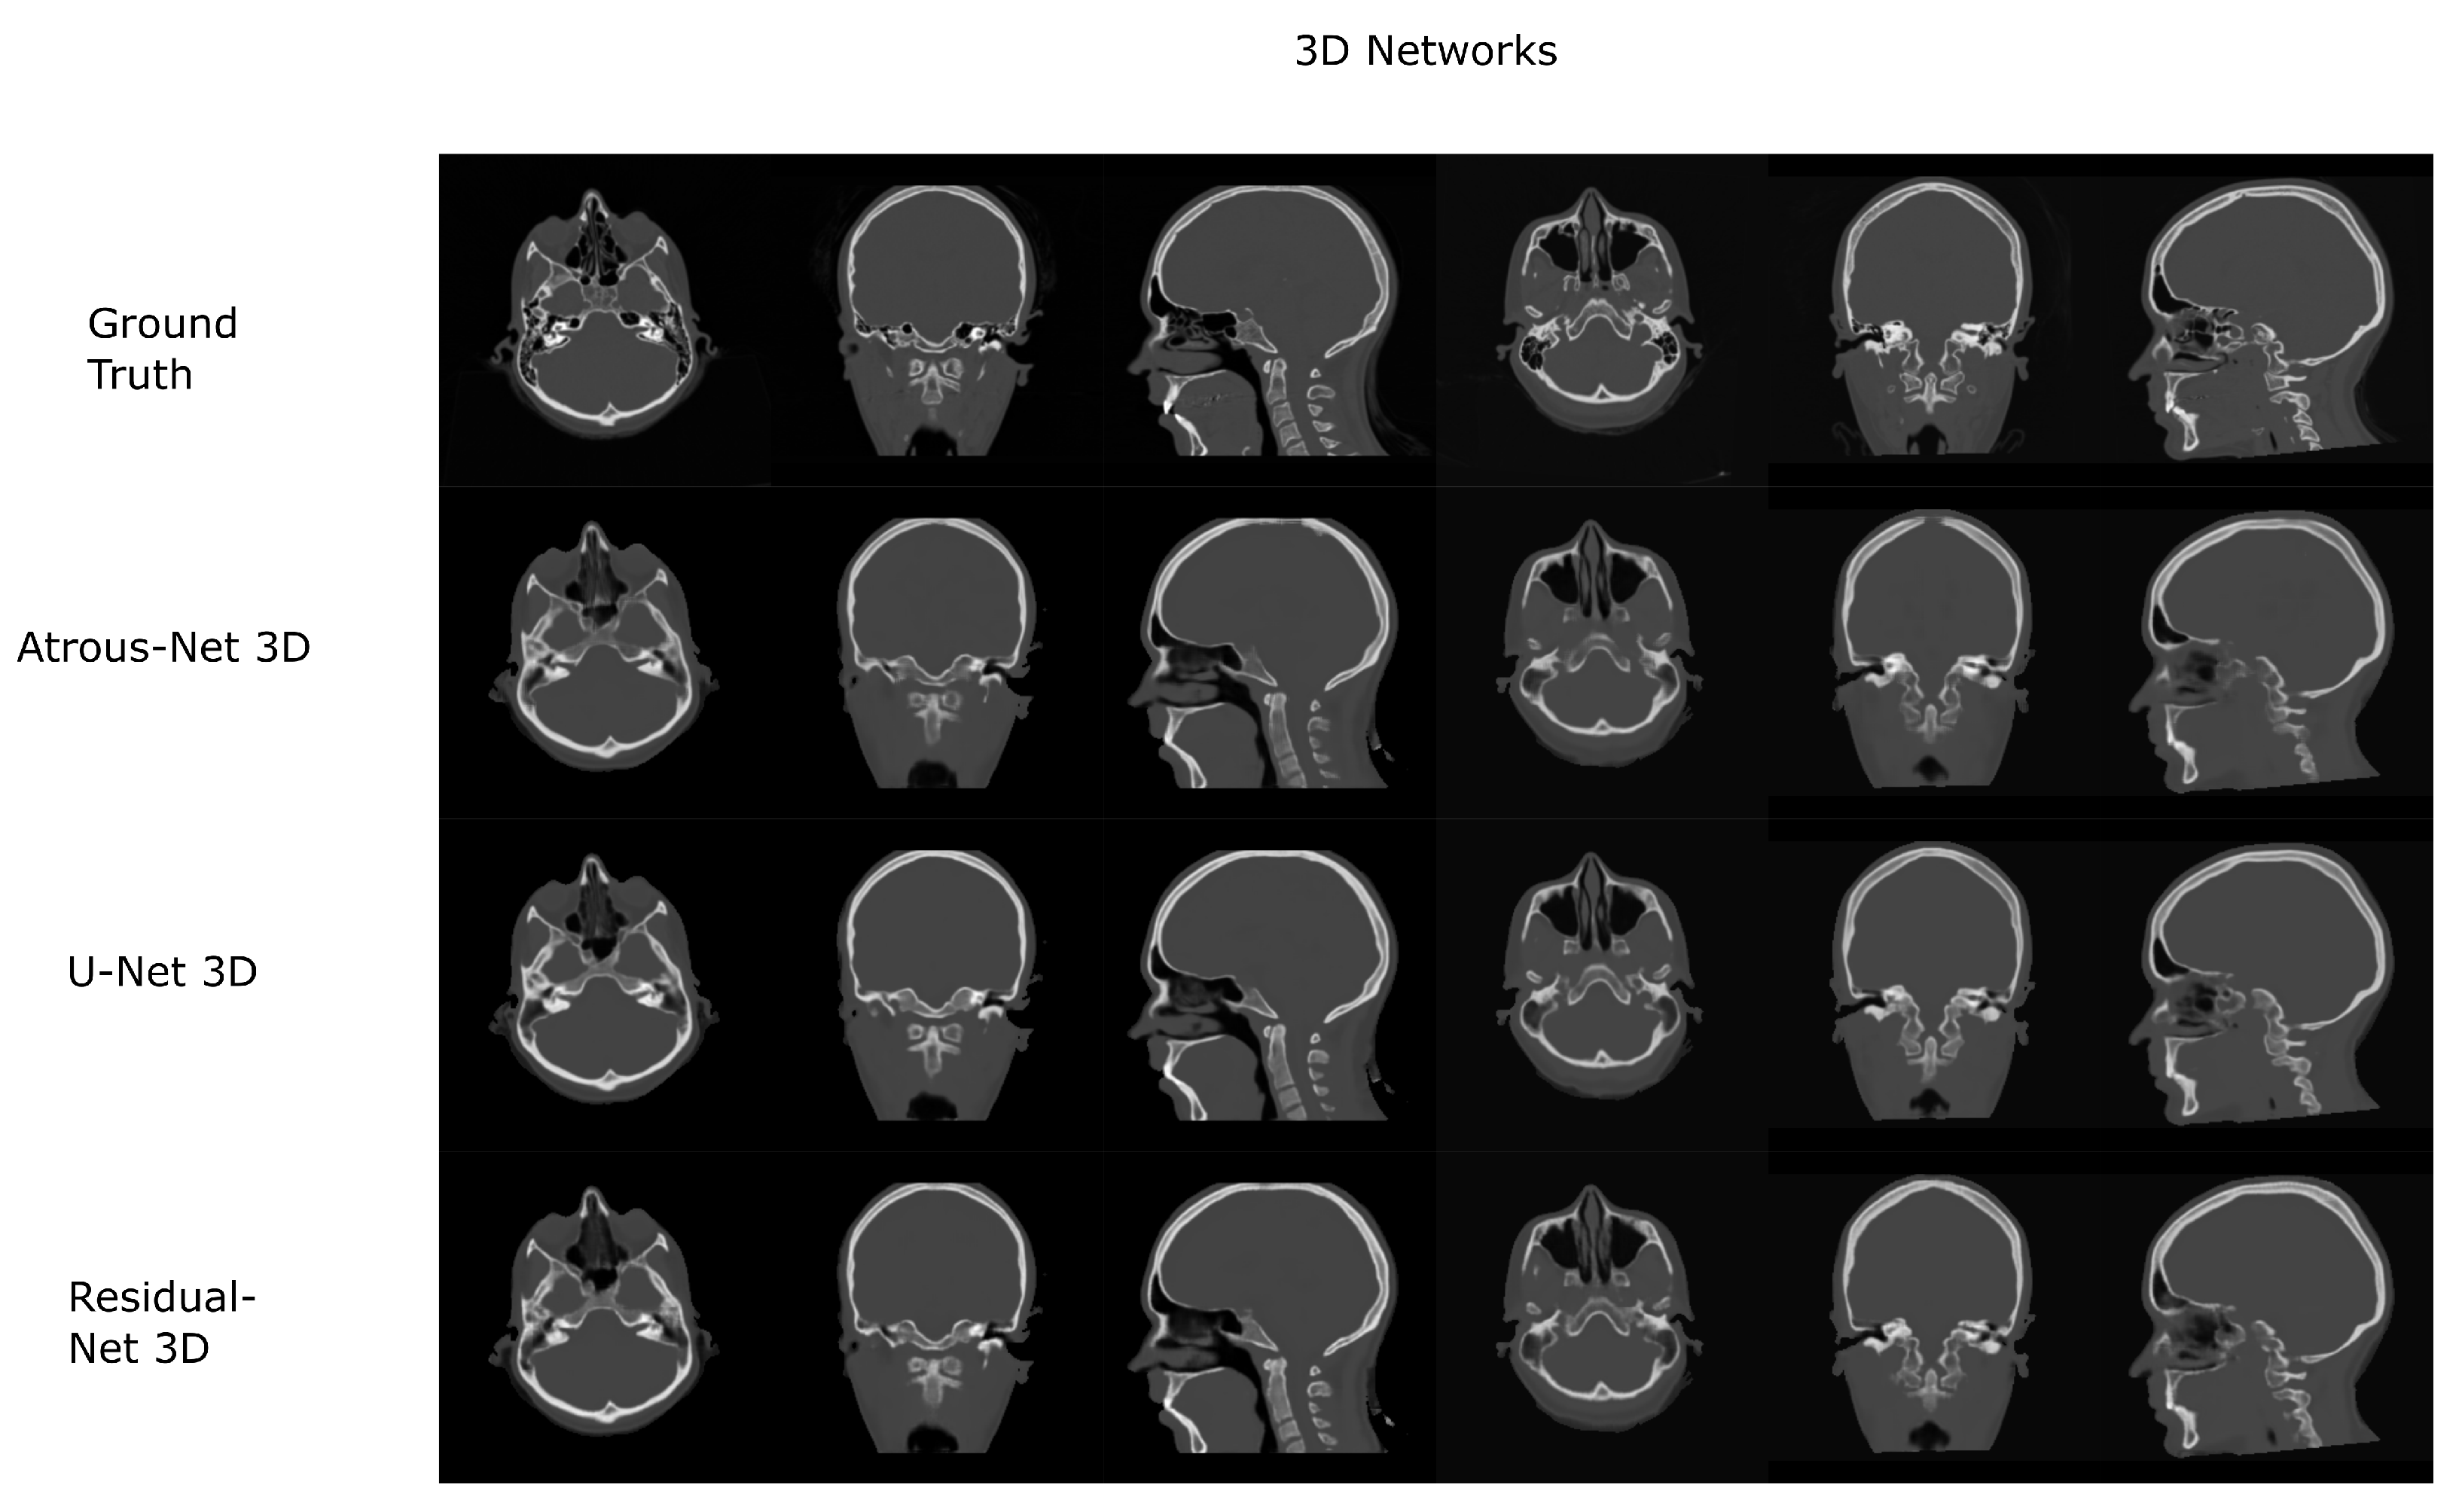

Figure 7.

Head results using 3D-16 networks.

The results for all tissues using the head dataset are depicted in Table 1, Table 2 and Table 3; the results using only the bone voxels are detailed in Table 4, Table 5 and Table 6; the results using only the fat voxels are detailed in Table 7, Table 8 and Table 9; and the results using only the soft-tissue voxels are detailed in Table 10, Table 11 and Table 12. The best performing 2D network for the head dataset was the Residual-net. The results presented a MAE of 99.83 HU, a PSNR of 24.83 and a Pearson Coefficient of 0.931 in all tissues, and a MAE of 326.33 HU, a PSNR of 19.04 and a Pearson Coefficient of 0.826 in bone voxels. The ANOVA test revealed a statistically significant effect of the 2D architectures for MAE results (all tissues: , ; bone: , ) and PSNR results (all tissues: = 99.3, ; bone: = 85.6, ). A paired t-test was used to compare the Residual-net to the other networks reporting also statistically significant differences in the MAE and in the PSNR (Table 13). Using 2D convolutions, the Atrous-net and the U-net performed 5% and 18% worse than the residual-net, respectively. Moreover, the U-net network was clearly behind the other networks using 2D convolutions. Nevertheless, the U-net in 3D-16 obtained a MAE of 89.54 HU, a PSNR of 25.69 and a Pearson Coefficient of 0.943 in all tissues, and a MAE of 289.10 HU, a PSNR of 20.05 and a Pearson Coefficient of 0.861 in bone voxels, which were the best results for the head dataset. The ANOVA test also reported a statistically significant effect of the 3D networks for the MAE (all tissues: ; bone , ) and the PSNR (all tissues: , ; bone: , ). The post hoc paired t-test that is depicted in Table 14 also reported statistically significant differences in the MAE and PSNR after comparing each architecture. Summarizing, the results using 3D convolutions from the U-net were 17% and 10% better than those of the Atrous-net and Residual-net, respectively. Visual result examples of head pseudo-CTs are depicted in Figure 6 and Figure 7. Table 15 shows the time needed to synthesize a whole head volume using the different architectures.

According to the results of the current work, there is no preferred network for every problem. Thus, the results depend on the specific anatomy defining the problem and the MRI sequence that is used. As shown in Section 4. Results, if the anatomy is similar to a head with complex bone structures and geometries, 2D schemes generate aliasing and artifacts across bone structures. Instead, 3D schemes and reconstructions with stride 16 provide bones with smooth boundaries, which is translated into a significant reduction of the error. Moreover, the best architecture to achieve the best detail in a head pseudo-CT is the 3D U-net (). When using 3D architectures, the input of the network is usually a 3D patch due to GPU memory limitations. 3D patches only depict a part of the anatomy. Therefore, they provide limited contextual information. In this case, the progressive spatial reduction and up-sampling of the feature maps are probably the best option, as it occurs in the U-net.